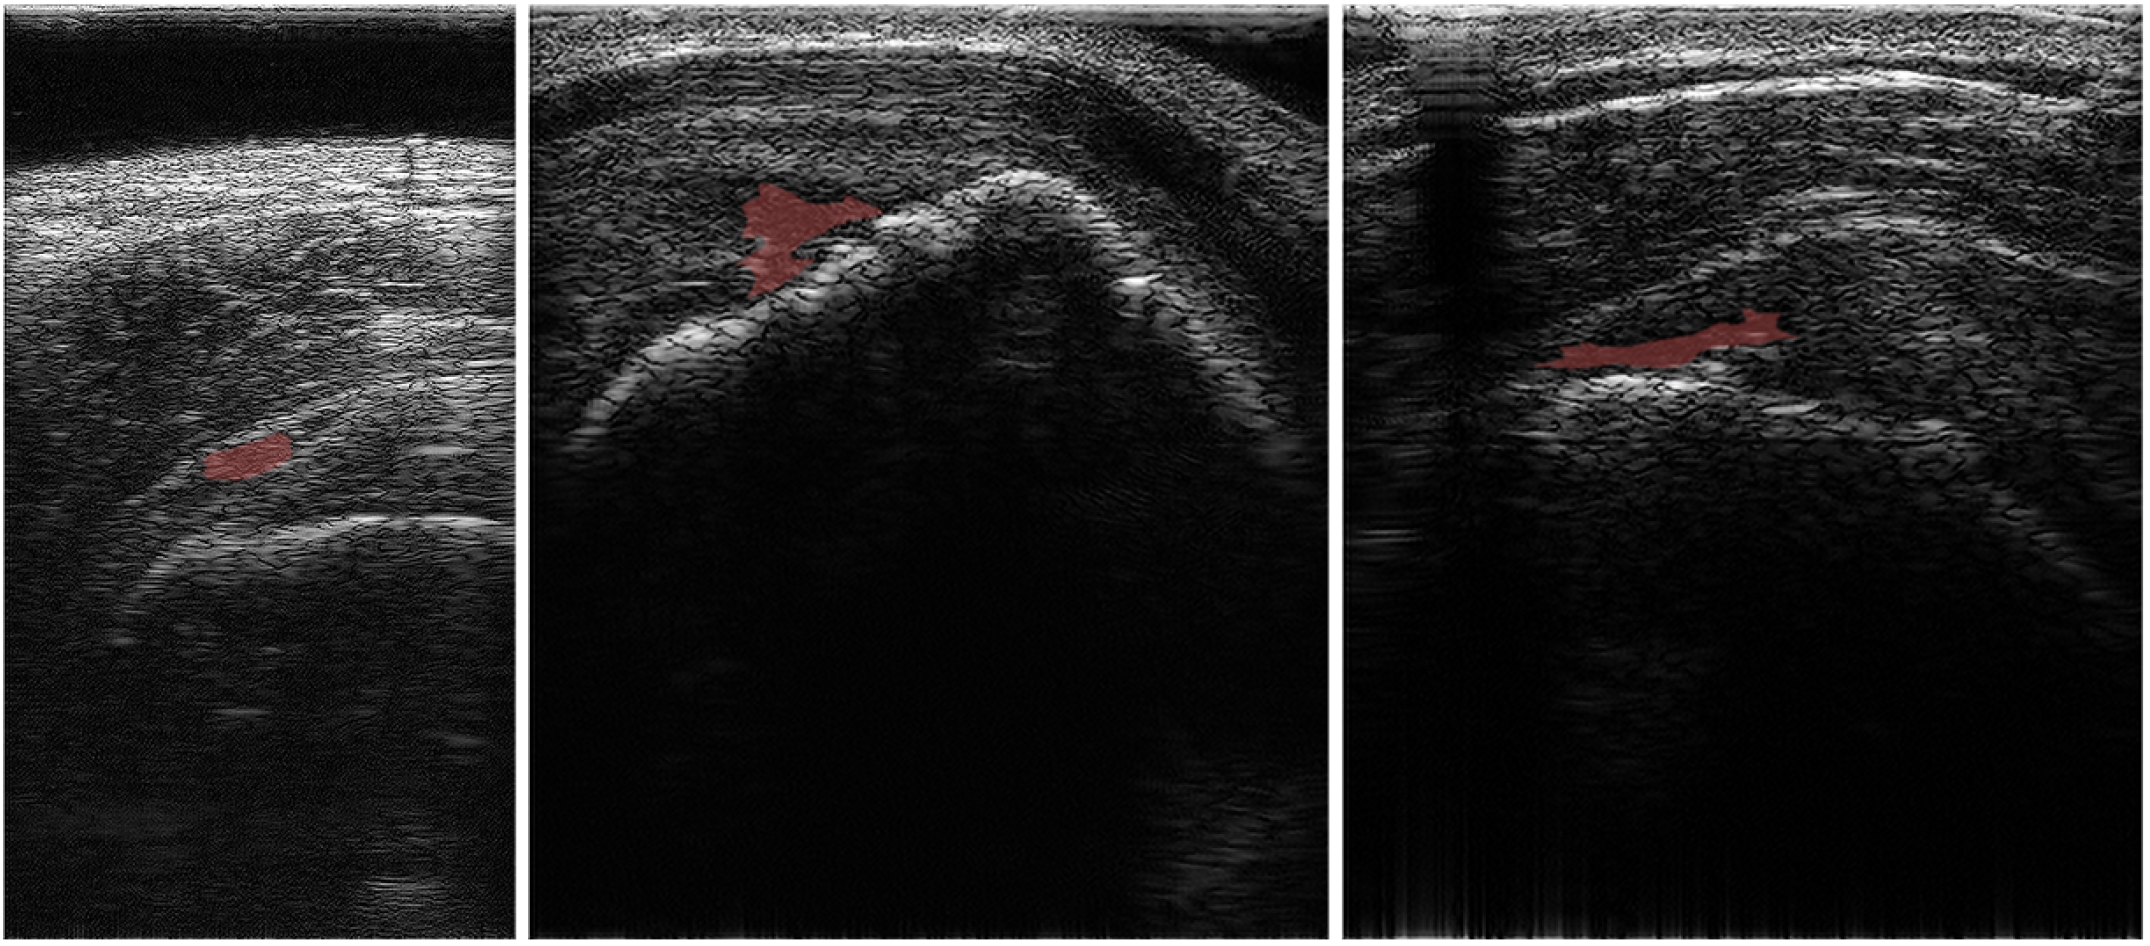

Real-time Self-supervised Ultrasound Image Enhancement Using Test-Time Adaptation for Sophisticated Rotator Cuff Tear Diagnosis

Medical ultrasound imaging is a key diagnostic tool across various fields, with computer-aided diagnosis systems benefiting from advances in deep learning. However, its lower resolution and artifacts pose challenges, particularly for non-specialists. The simultaneous acquisition of degraded and high-quality images is infeasible, limiting supervised learning approaches. Additionally, self-supervised and zero-shot methods require extensive processing time, conflicting with the real-time demands of ultrasound imaging. Therefore, to address the aforementioned issues, we propose real-time ultrasound image enhancement via a self-supervised learning technique and a test-time adaptation for sophisticated rotational cuff tear diagnosis. The proposed approach learns from other domain image datasets and performs self-supervised learning on an ultrasound image during inference for enhancement. Our approach not only demonstrated superior ultrasound image enhancement performance compared to other state-of-the-art methods but also achieved an 18\% improvement in the RCT segmentation performance.